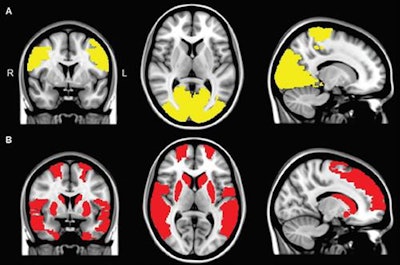

Functional MR images show reduced regional connectivity in Parkinson's patients (A) and in Parkinson's patients with visual hallucinations (B). A regional functional connectivity analysis revealed lower connectivity in patients with visual hallucinations and in patients without hallucinations, compared with control subjects, in the paracentral and occipital regions (yellow areas in A). Functional connectivity in the frontal, temporal, and subcortical regions was exclusively lower in Parkinson's patients with visual hallucinations, compared with controls (red areas in B). Images courtesy of Radiology.The differences between Parkinson's patients and the controls were further detailed in the review of the cognitive tests. Global cognitive functioning scores in the CCE test were significantly lower among all Parkinson's patients than for the control participants (p = 0.004), but the results were comparable between the groups (p = 0.721) for the MMSE test.

In addition, Parkinson's patients with visual hallucinations had reduced functional connectivity compared with the control subjects in nine brain regions. The underperforming regions were in the frontal cortex, temporal cortex, rolandic operculum, occipital cortex, and striatum and were related to cognitive deficits.

The regional connectivity analysis showed eight regions in the occipital lobe and paracentral area where functional connectivity was less for both Parkinson's patients with and without visual hallucinations, compared with the control participants. These regions are associated with motor performance.